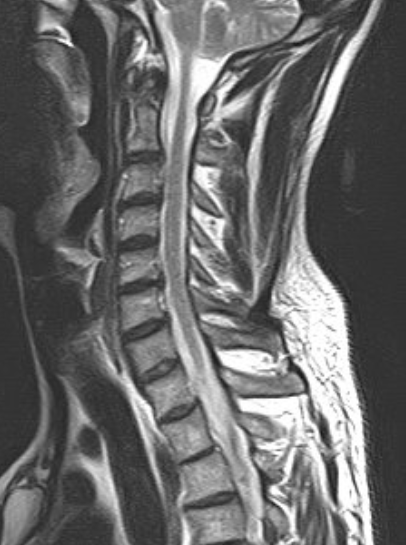

DIAGNOSI:

Ernia discale cervicale c5-c6

Risonanza magnetica cervicale pre-operatoria

Intervento chirurgico eseguito:

Microdiscectomia cervicale con approccio anteriore + introduzione di cage intersomatica cervicale

Radiografia cervicale post-operatoria